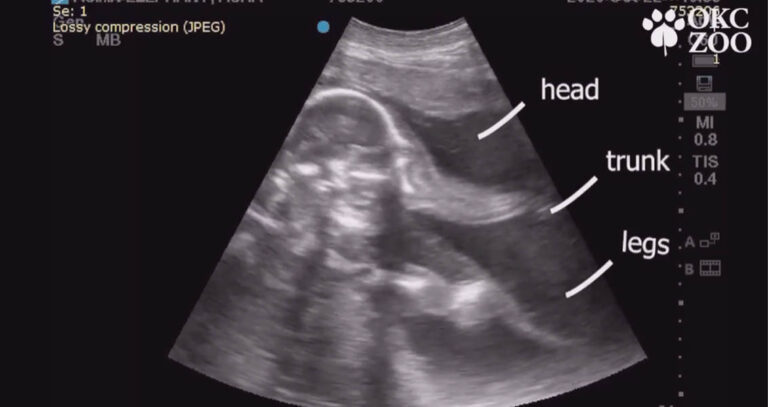

A tiny trunk and little legs? This ultrasound is ultra-sweet! The Oklahoma City Zoo is thankful for 25-year-old Asha’s growing Asian elephant calf, due in February 2022 ?

People on the internet were amazed by the ultrasound video showing vivid details of the unborn animal. You can easily identify the head, trunk and legs from the ultrasound result. For many people, this is actually their first time seeing an ultrasound of a baby elephant. So, it’s no surprise that the post quickly went viral.